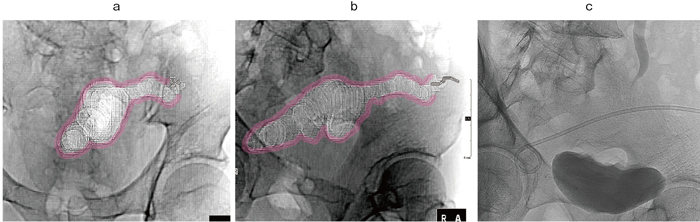

図3 術後膿瘍症例

抜去したドレーンのtractに沿って膿瘍を形成。膿瘍腔の広がりを仮想透視画像で表示し(a)、tractを長軸でとらえられるworking angleを確認(b)。同角度の透視下手技 (c)にてtractの最も深い部分にドレナージチューブを留置した。